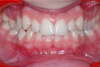

Des cas complexes nécessitant l’extraction de dents définitives (Fig. 3)

Figure 3 — Cas d’extraction de deux prémolaires supérieures traité en technique lingual